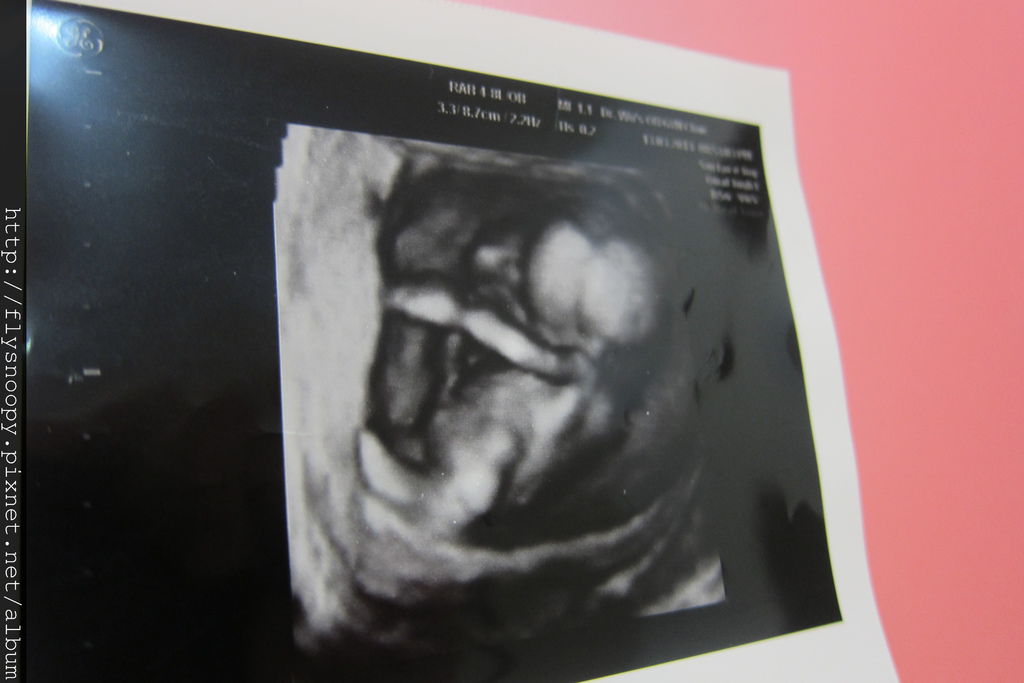

BPD(胎兒頭骨橫徑):9cm

EFW(預估體重):108g

現在可以很清楚看見baby的手腳,baby正在玩自己的手耶

4D的照片還不是很好看

醫生說baby大一點會更漂亮喔,期待